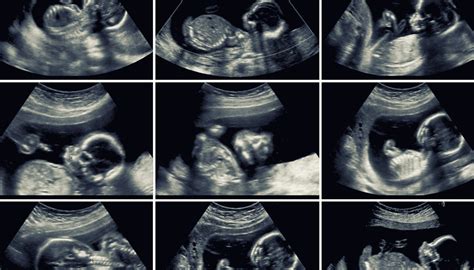

Morfologický ultrazvuk, často označovaný aj ako genetický ultrazvuk, predstavuje jedno z najdôležitejších ultrazvukových vyšetrení počas tehotenstva. Vykonáva sa zvyčajne medzi 18. až 22. týždňom tehotenstva, pričom optimálna fáza na toto podrobné vyšetrenie plodu je okolo 20. týždňa. Toto vyšetrenie nadväzuje na skríning v prvom trimestri, ale je možné ho absolvovať aj v prípade, že predchádzajúce vyšetrenia neboli vykonané.

Okolie 20. týždňa tehotenstva je ideálne z viacerých dôvodov. V tomto období bývajú optimálne akustické podmienky na vyšetrenie, ktoré sú dané primeraným pomerom veľkosti tela plodu a dostatočného množstva plodovej vody. Prítomnosť plodovej vody umožňuje z fyzikálneho hľadiska detailné vyšetenie plodu.

Morfologický ultrazvuk umožňuje detailne skenovať jednotlivé časti plodu a všetky jeho orgány. Pod drobnohľadom sú orgány ako mozog, srdce, pľúca, žalúdok, črevá, obličky, pečeň, močový mechúr, ako aj vývoj chrbtice, končatín a častí tváre dieťatka. Sleduje sa aj placenta - jej štruktúra a lokalizácia, a zisťuje sa množstvo plodovej vody. Toto vyšetrenie tiež umožňuje určiť pohlavie dieťatka a presnejší termín pôrodu.

Základné morfologické ultrazvuky sa štandardne robia v 2D forme, ktorá je dostatočná na zistenie všetkých potrebných údajov o plode. 3D ultrazvuk predstavuje statické trojrozmerné zobrazenie plodu, ktoré sa dosahuje počítačovým spracovaním 2D obrazov. 4D zobrazenie pridáva k 3D obrazu časový rozmer, teda pohyb v reálnom čase, čo umožňuje sledovať, ako sa dieťa hýbe a aké má mimické prejavy.